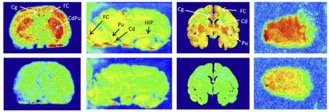

β Change in Expression of 5-HT 6 Receptor at Different Stages of Alzheimer’s Disease: A Postmortem Study with the PET Radiopharmaceutical [ 18F]2FNQ1P

P. Courault, S. Emery, S. Bouvard, F. Liger, F. Chauveau, D. Meyronet, A. Fourier, T. Billard, L. Zimmer, S. Lancelot

J. Alzheimer's Dis. 2020, 75, 1329-1338.